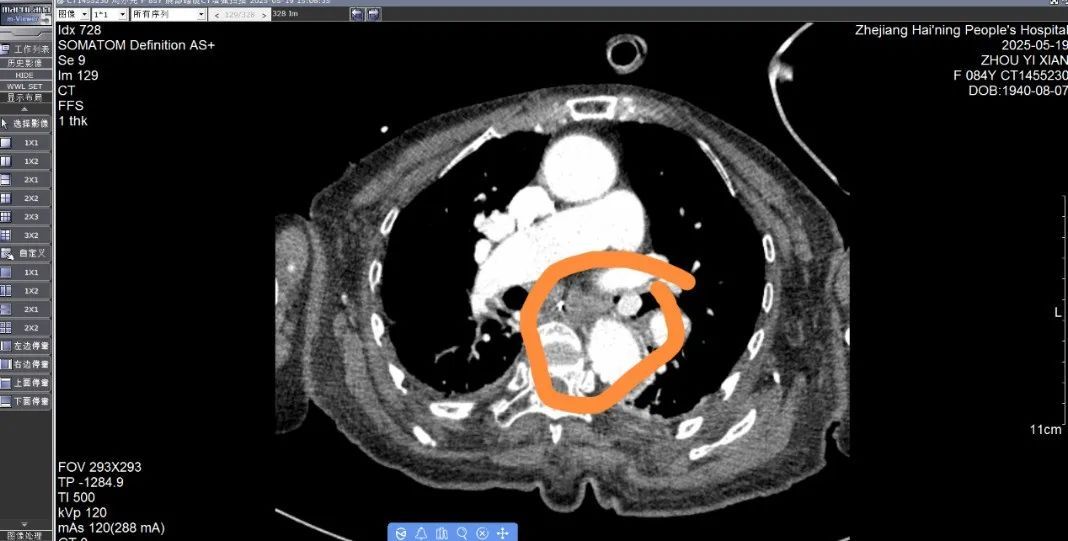

温医大附二院呼吸内科副主任医师夏晓东介绍,当时通过初步检查判断,枇杷核是卡在右侧支气管里,需要立即手术取出,不然会有危险。之后,医生通过气管镜,将导管从徐大爷的鼻腔直接插入右侧支气管,找到枇杷核的位置,顺利取出枇杷核(直径约1.5厘米),花了约5分钟。术后,徐大爷的症状得以缓解,在院观察了一晚后便回家了。夏晓东说,支气管是气管的分支,分为左右支气管,病人还是比较幸运的,如果卡在气管里,那可能当场就导致窒息。